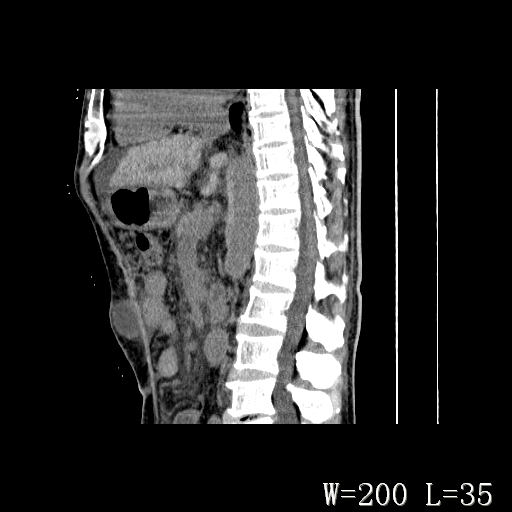

男,52岁,门脉高压断流术后1年,发现腹部肿物2月。

1)前腹壁中线区(脐上方)囊性占位性病变,考虑淋巴囊肿。2)腹水。